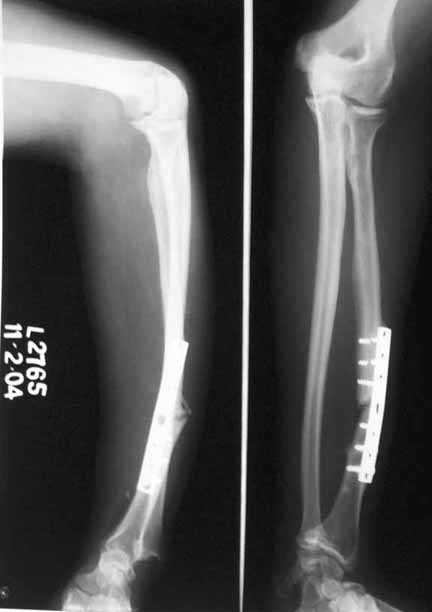

This is a case of ununited Galeazzi injury with implant failure in a middle aged healthy adult male. Patient suffered this injury four years ago and was operated elsewhere. He was later advised bonegrafting which he did not comply with. At present he has pain and deformity. Also the implant has given way with breakage of screws in the proximal part and DRUJ disruption. I would welcome your opinion on further management: 1) On implant removal, specially the broken screws, 2) Type of fixation and 3) DRUJ management.

1. remove implant and leave the screws. 2. repeat plate and screw fixation, I most likely would use a locked plating system with bone graft. 3. DRUJ: reduction and pin fixation if needed.